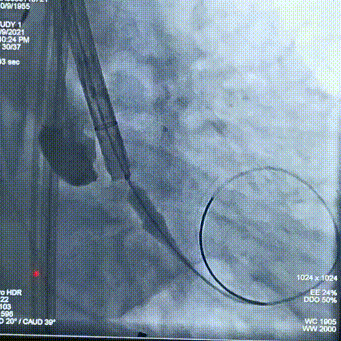

主动脉CT

主动脉瓣环平均直径:22.1mm;

左室流出道平均直径:23.7;

左冠脉开口:12.3mm;

右冠脉开口高度:11.2mm。

术前讨论:患者为三叶瓣主狭,左右冠瓣叶长,开口低,瓦氏窦小,左右冠高风险。

袁义强院长总结了该病例特点:三叶瓣,左右冠均高风险,解剖适合TAVR,年龄73岁,存在明确TAVR手术适应症。选择右股动脉入路,根据CT测量分析选择瓣膜大小,窦部情况可,瓣环平均直径22.1mm,计划22号球囊预扩,评估冠脉风险,选择植入24mm瓣膜。

右股动脉入路、22球囊扩张,植入24型号瓣膜;

监护麻醉,经右侧股动脉全麻行TAVR,选用22mm球囊扩张,查看冠脉风险,VitaFlow24瓣膜植入。

球囊预扩

瓣膜定位

经评估后植入左主干烟囱支架